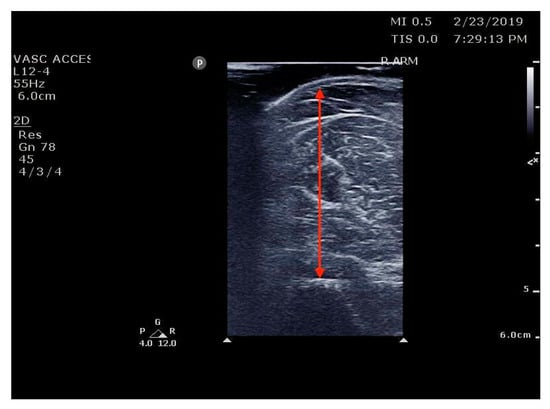

The Principal Investigator (PI), co-investigators, and RAs were trained with a 2 h lecture and a 4 h hands-on training session given by a POCUS-certified instructor from the Division of Emergency Ultrasound. Post-training, the intraclass correlation (ICC) [25,26] of sonographic measurements of the biceps and thigh muscle between the research team was 0.92. The research team included two emergency physicians, three EM Advanced practice practitioners with ultrasound experience, three EM ultrasound fellows, and two geriatric research fellows who are emergency physicians (Figure 1 and Figure 2).

Figure 2.

Ref. [33] Thigh muscle thickness measurement. ST = subcutaneous tissue; RF = rectus femoris; VI = vastus intermedius; QT; quadricep’s thickness.

RAs asked participants about their history of falls and fall-risk factors and then measured the thickness of upper and lower limb muscles using POCUS as well as measured grip strength, and they asked the patients’ cooperation to do the Timed up and go (TUG) test. We used the standard POCUS ultrasound machines (Mindray, TE7, 2019) and linear transducer with a frequency range of 2–8 MHz available in the ED to measure the muscle thickness of each patient’s upper and lower extremities on their dominant side. Following Perkisas, the biceps landmark was the midpoint between the acromion process and the elbow crease at the anatomical position [29,40]. The thigh muscle (rectus femoris/vastus intermedius) landmark was the midpoint between the anterior superior iliac spine and the proximal patella at the anatomical position [41,42]. Participants were instructed to lie down on the couch with their hips and knees extended against the couch. A copious amount of water-soluble gel was applied to the skin to avoid pressure on the muscle. The RA measured the muscle by including the muscle belly and fascia and excluding subcutaneous adipose tissue or skin and stored the images in the protected hospital cloud data storage system.